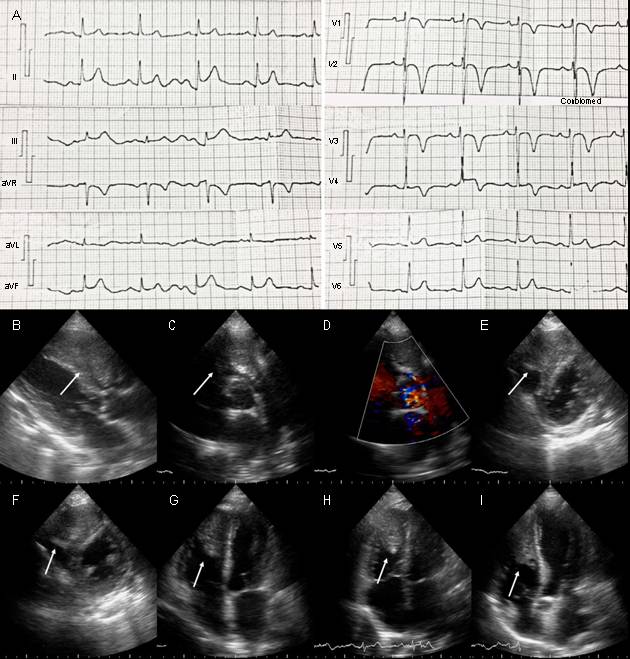

93 lpm, frecuencia respiratoria de 26 rpm, presión arte- rial 110/80 mmHg. A la auscultación cardiaca presentaba soplo eyectivo en foco pulmonar grado III/VI, irradiado a foco aórtico accesorio, eyectivo, grado III/IV. En la auscultación pulmonar se encontraron crepitantes finos y gruesos basales bilaterales. En ECG se observó elevación del punto J y ondas T negativas, simétricas de V1 a V4 y discreta elevación de ST en cara inferior (fig. 1). Tiene como ante- cedente imagen quística gigante en riñón derecho, a la cual realizaron en diversas oportunidades drenaje percutáneo, pero no realizaron biopsia ni indicaron otro tratamiento. También refirió infecciones respiratorias a repetición, con último episodio dos semanas antes de la hospitalización. En la radiografía de tórax se observaron imágenes redondeadas de aspecto algodonoso con distribución difusa en ambos campos pulmonares. Se solicitaron enzimas cardiacas y se encontraron dentro de límites normales en tomas seriadas; dímero D resultó negativo. Se realizó ecocardiograma transtorácico donde se observó el ventrículo izquierdo (VI) no dilatado con patrón geométrico normal y fracción de eyección preservada, sin trastornos de cinesia regional; el ventrículo derecho (VD) no dilatado con función sistólica preservada, con imagen ecorrefringente adherida al ápex del VD, de 36x20 mm aproximadamente, que se extendía hasta el tracto de salida del VD; presión sistólica de la arteria pulmonar normal. Ante tales hallazgos, se solicitó resonancia magnética de tórax y abdomen, con contraste (fig. 2), que reportó lesión ocupante de espacio (LOE) heterogénea en cavidad del VD, de gran tamaño 41x79x24 mm, que infiltraba las paredes y ocasionaba disrupción del pericardio visceral, con bordes irregulares; generando obstrucción dinámica del tracto de salida del VD. Realce tardío heterogéneo con áreas de baja señal de intensidad en relación con necrosis tumoral y hemorragia. Se planteó sarcoma indiferenciado o lesión metastásica. Riñón derecho con pérdida de la morfología, lesión sólida heterogénea de bordes mal definidos, 6.9x5.8 cm. En ambos pulmones, imágenes nodulares múltiples, con diámetros entre 0.5 y 2 cm, de distribución aleatoria, algunas con contacto pleural y con realce significativo de todas las lesiones.

Figura : A) Electrocardiograma del paciente donde se observa elevación del punto J y ondas T negativas, simétricas de V1 a V4 y discreta elevación de ST en cara inferior (II, III y AVF). B-I) Ecocardiograma transtorácico. B) Eje paraesternal largo, se observa imagen ecorrefringente dentro de gran parte de la cavidad del VD (flecha). C y D) Eje paraesternal corto al nivel de los grandes vasos, tumor en el tracto de salida del VD (flecha), con obstrucción dinámica vista por Doppler color D). E y F) Eje paraesternal corto al nivel de la valvular mitral y músculos papilares respectivamente. Se puede ver LOE en más del 50% del VD (flechas). G y H) Vista de 4 cámaras y 4 cámaras modificado, donde se observa tumor intracavitario adherido al ápex y pared lateral del VD, y al septum interventricular (flecha). I) Vista de 5 cámaras. Se observa la extensión del tumor dentro del VD y el septum interventricular (flecha).

Aun cuando no hay afectación de arterias coronarias, las metástasis en miocardio y pericardio podrían simular un síndrome coronario agudo, inclusive con elevación de biomarcadores cardiacos y alteraciones del segmento ST y la onda T en el ECG1,5. Otros mecanismos sugeridos para estos cambios son: lesión miocárdica continua que evita formación de nueva membrana celular, estiramiento de fibras musculares adyacentes, reacción inflamatoria, cambio en el gradiente Na-K transmembrana y transferencia de K del tejido dañado al miocardio adyacente produciendo diferencias en los potenciales eléctricos6. En este caso había alteraciones del ST en cara inferior y del punto J y onda T en cara anteroseptal, sin embargo, las enzimas cardiacas normales, y dímero D negativo, orientó a que los cambios en ECG no estaban asociados a infarto agudo de miocardio o embolismo pulmonar, pero podrían estar relacionados con la afectación del ápex y del septum interventricular a pesar de que el tumor se infiltró principalmente en VD.